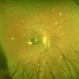

- Angiod streaks in Pseudoxanthoma elasticum

- Right eye of a 43 year female patient came with blurring of vision of right eye since 2 years. There was loose redundant skin in the neck and axilla. Angiod streaks were in a spider web appearance .Vision was 1/60 in right eye and 6/9 in left eye. Right macula showed a sub retinal scar with pigmentation.